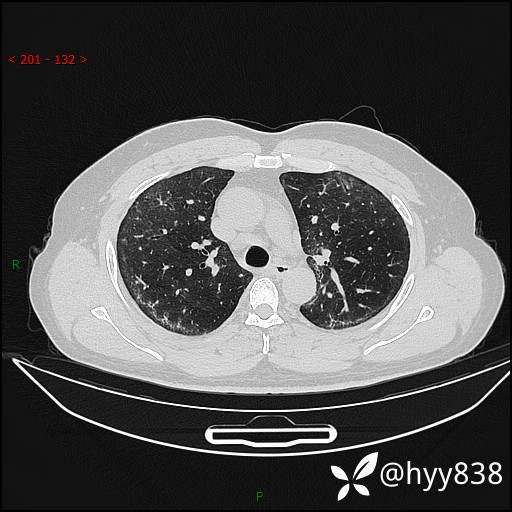

第二次CT(7天后)